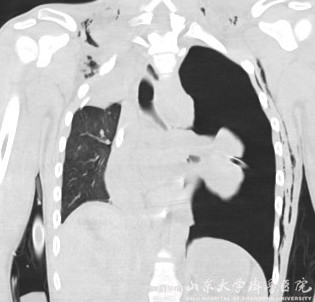

5月29日上午,在ECMO 平稳转机下,相应检查和治疗陆续开始,气管镜室主治医师李陶首先在床旁给予患者行支气管镜检查,随后进行肺部CT和气管树的重建,胸外科吴铭生教授及赵健教授到床边仔细检查了患者,并与重症医学科和麻醉科详细讨论,决定当天下午开胸进行肺叶切除手术或者气管破裂修补术。下午6时半,患者在ECMO辅助下前往手术室,麻醉顺利,开胸后发现患者损伤确切部位为左主支气管根部断裂大约4.5cm,断裂部位距离气管隆突很近,气管断裂部位炎症水肿明显,手术修补难度极大,术后出现吻合口瘘的可能性极高。遂向副院长田辉汇报病情后,田辉从家中赶来亲自上台检查情况后,商量决定进行左肺全切除、左主支气管结扎术。手术结束时,又到了次日的凌晨,患者在ECMO支持下安返病房。